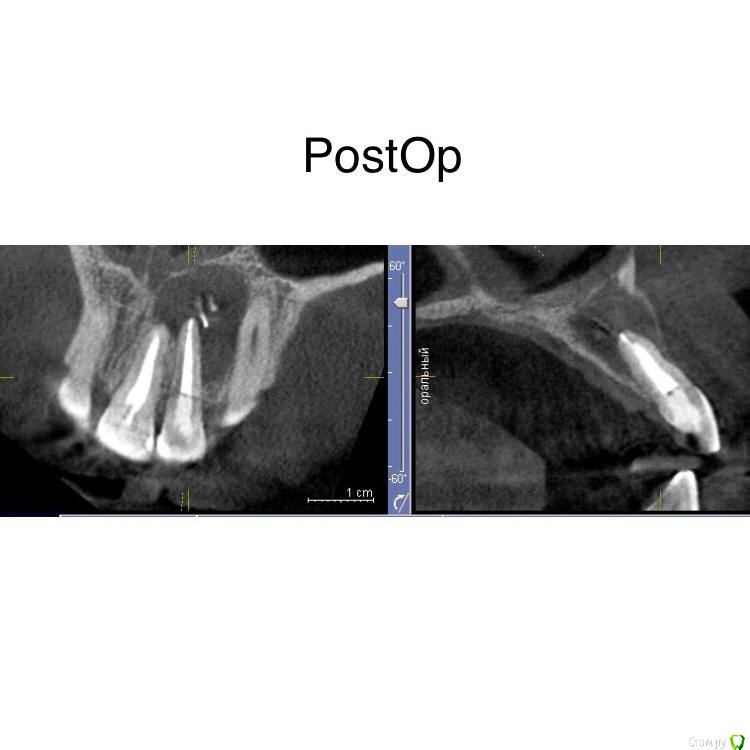

Marika Опубликовано 22 декабря, 2017 Поделиться Опубликовано 22 декабря, 2017 Да. Пациент приедет через полгода на кт. Тоже выложу сюда.Спасибо, интересно понаблюдать за верхушкой. Ссылка на комментарий

Гарриевич Опубликовано 22 декабря, 2017 Автор Поделиться Опубликовано 22 декабря, 2017 я Бы сделал кт и оба перебрал 1 Ссылка на комментарий

Marika Опубликовано 22 декабря, 2017 Поделиться Опубликовано 22 декабря, 2017 Если на кт пойдет,там легче будет. Посмотрите сами , да и ему наглядно. Ссылка на комментарий

Marika Опубликовано 23 декабря, 2017 Поделиться Опубликовано 23 декабря, 2017 Спасибо), ждем кт. 1 Ссылка на комментарий

Гарриевич Опубликовано 2 октября, 2018 Автор Поделиться Опубликовано 2 октября, 2018 пришло время отчета 5 Ссылка на комментарий